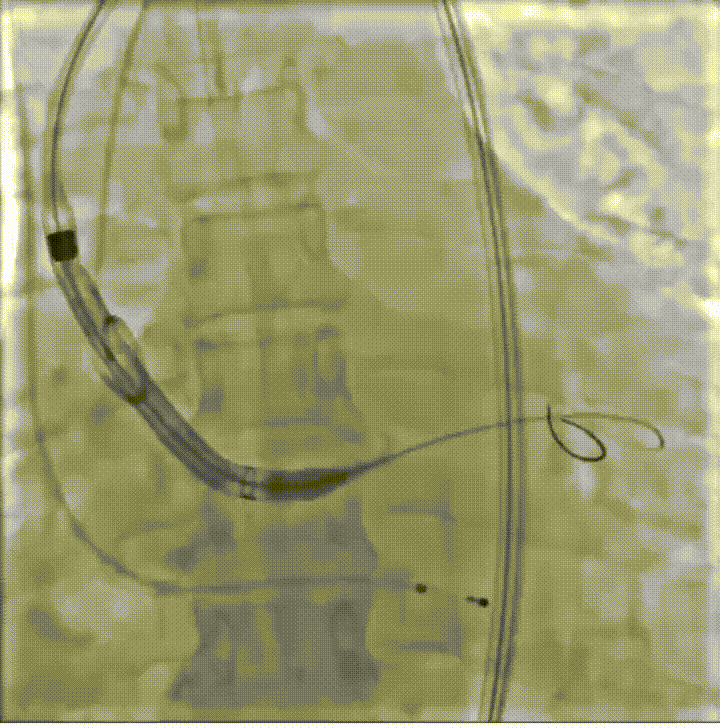

病例概览

患者病史 体检发现心脏瓣膜病半月余,平素无症状 ,有高血压病史。 后来院复查诊断为:主动脉瓣狭窄(重度)、先天性主动脉瓣二叶瓣畸形、心室肥厚、升主动脉扩张心功能 I 级(NYHA 分级)、高血压病 2 级(极高危)。 术前 CT:Type0型二叶瓣,瓣叶增厚,无钙化,类风湿性;瓣环径25.6mm,LVOT稍收窄,瓣环水平夹角66.6°,轻微横位心;左右冠开口高度可,瓣叶不长,无冠脉风险;心室收缩末内径约32mm,室壁增厚;外周入路无明显迂曲,无钙化、双侧内径可、双股中分叉,右侧为主入路能够支持20F大鞘通过。 造影角度及入路:LAO 6° CAU 13° 手术策略 采用右侧股动脉为主入路,左侧为辅助入路,常规穿刺。推荐使用20球囊预扩,预装TAV29瓣膜,初始定位对齐瓣环上0mm开始释放。 手术过程 20号球囊预扩无明显腰征 输送器过弓跨瓣顺滑 80%工作位观察 术后造影,瓣膜释放位置良好,无瓣周漏 术后超声:人工生物瓣释放后形态满意,瓣叶开放、关闭活动良好,无瓣周漏;跨瓣血流速度降至 2.5m/s,平均压力梯度6mmHg,符合手术预期。 Prostyle A®预装干瓣——“刚柔并济”助力临床最优化解决方案: 丝滑过弓能力:Prostyle A®短瓣架设计联合远端超滑亲水涂层,即使没有联合使用snare,都可以柔顺过弓,该例横位心的患者更好的展现了输送系统的柔顺性; 平衡的径向支撑力:该例患者Type0型二叶瓣,术后形态展开良好且无瓣周漏,在横位心等复杂情况下实现稳定锚定。 80%可回收设计:80%工作位观察,起搏时间更短,对患者损伤减少到最小,也利于术中精准调整瓣膜位置,保证术后效果。